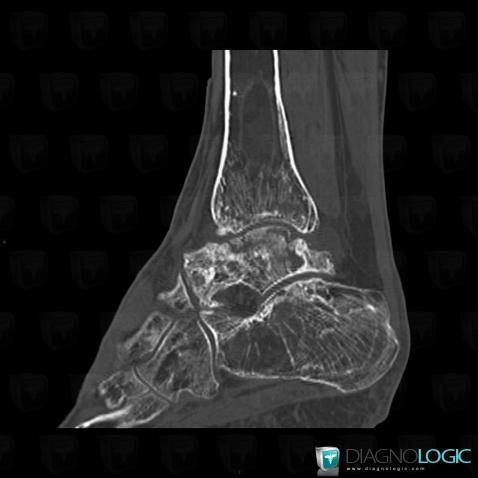

Bone infarct, Tibia - Distal part, CT

Here is the specific information in the key image above:

- Diagnosis Bone infarct, Location(s) Tibia - Distal part, with gamuts Mulltiple osteolysis, Multiple osteosclerotic bone lesions

Avascular necrosis, Tibia - Distal part, CT

- Diagnosis Avascular necrosis, Location(s) Tibia - Distal part, with gamuts Ill-defined osteolysis

- Diagnosis Bone infarct, Location(s) Tibia - Mid part, with gamuts Mulltiple osteolysis, Diaphyseal osteolysis